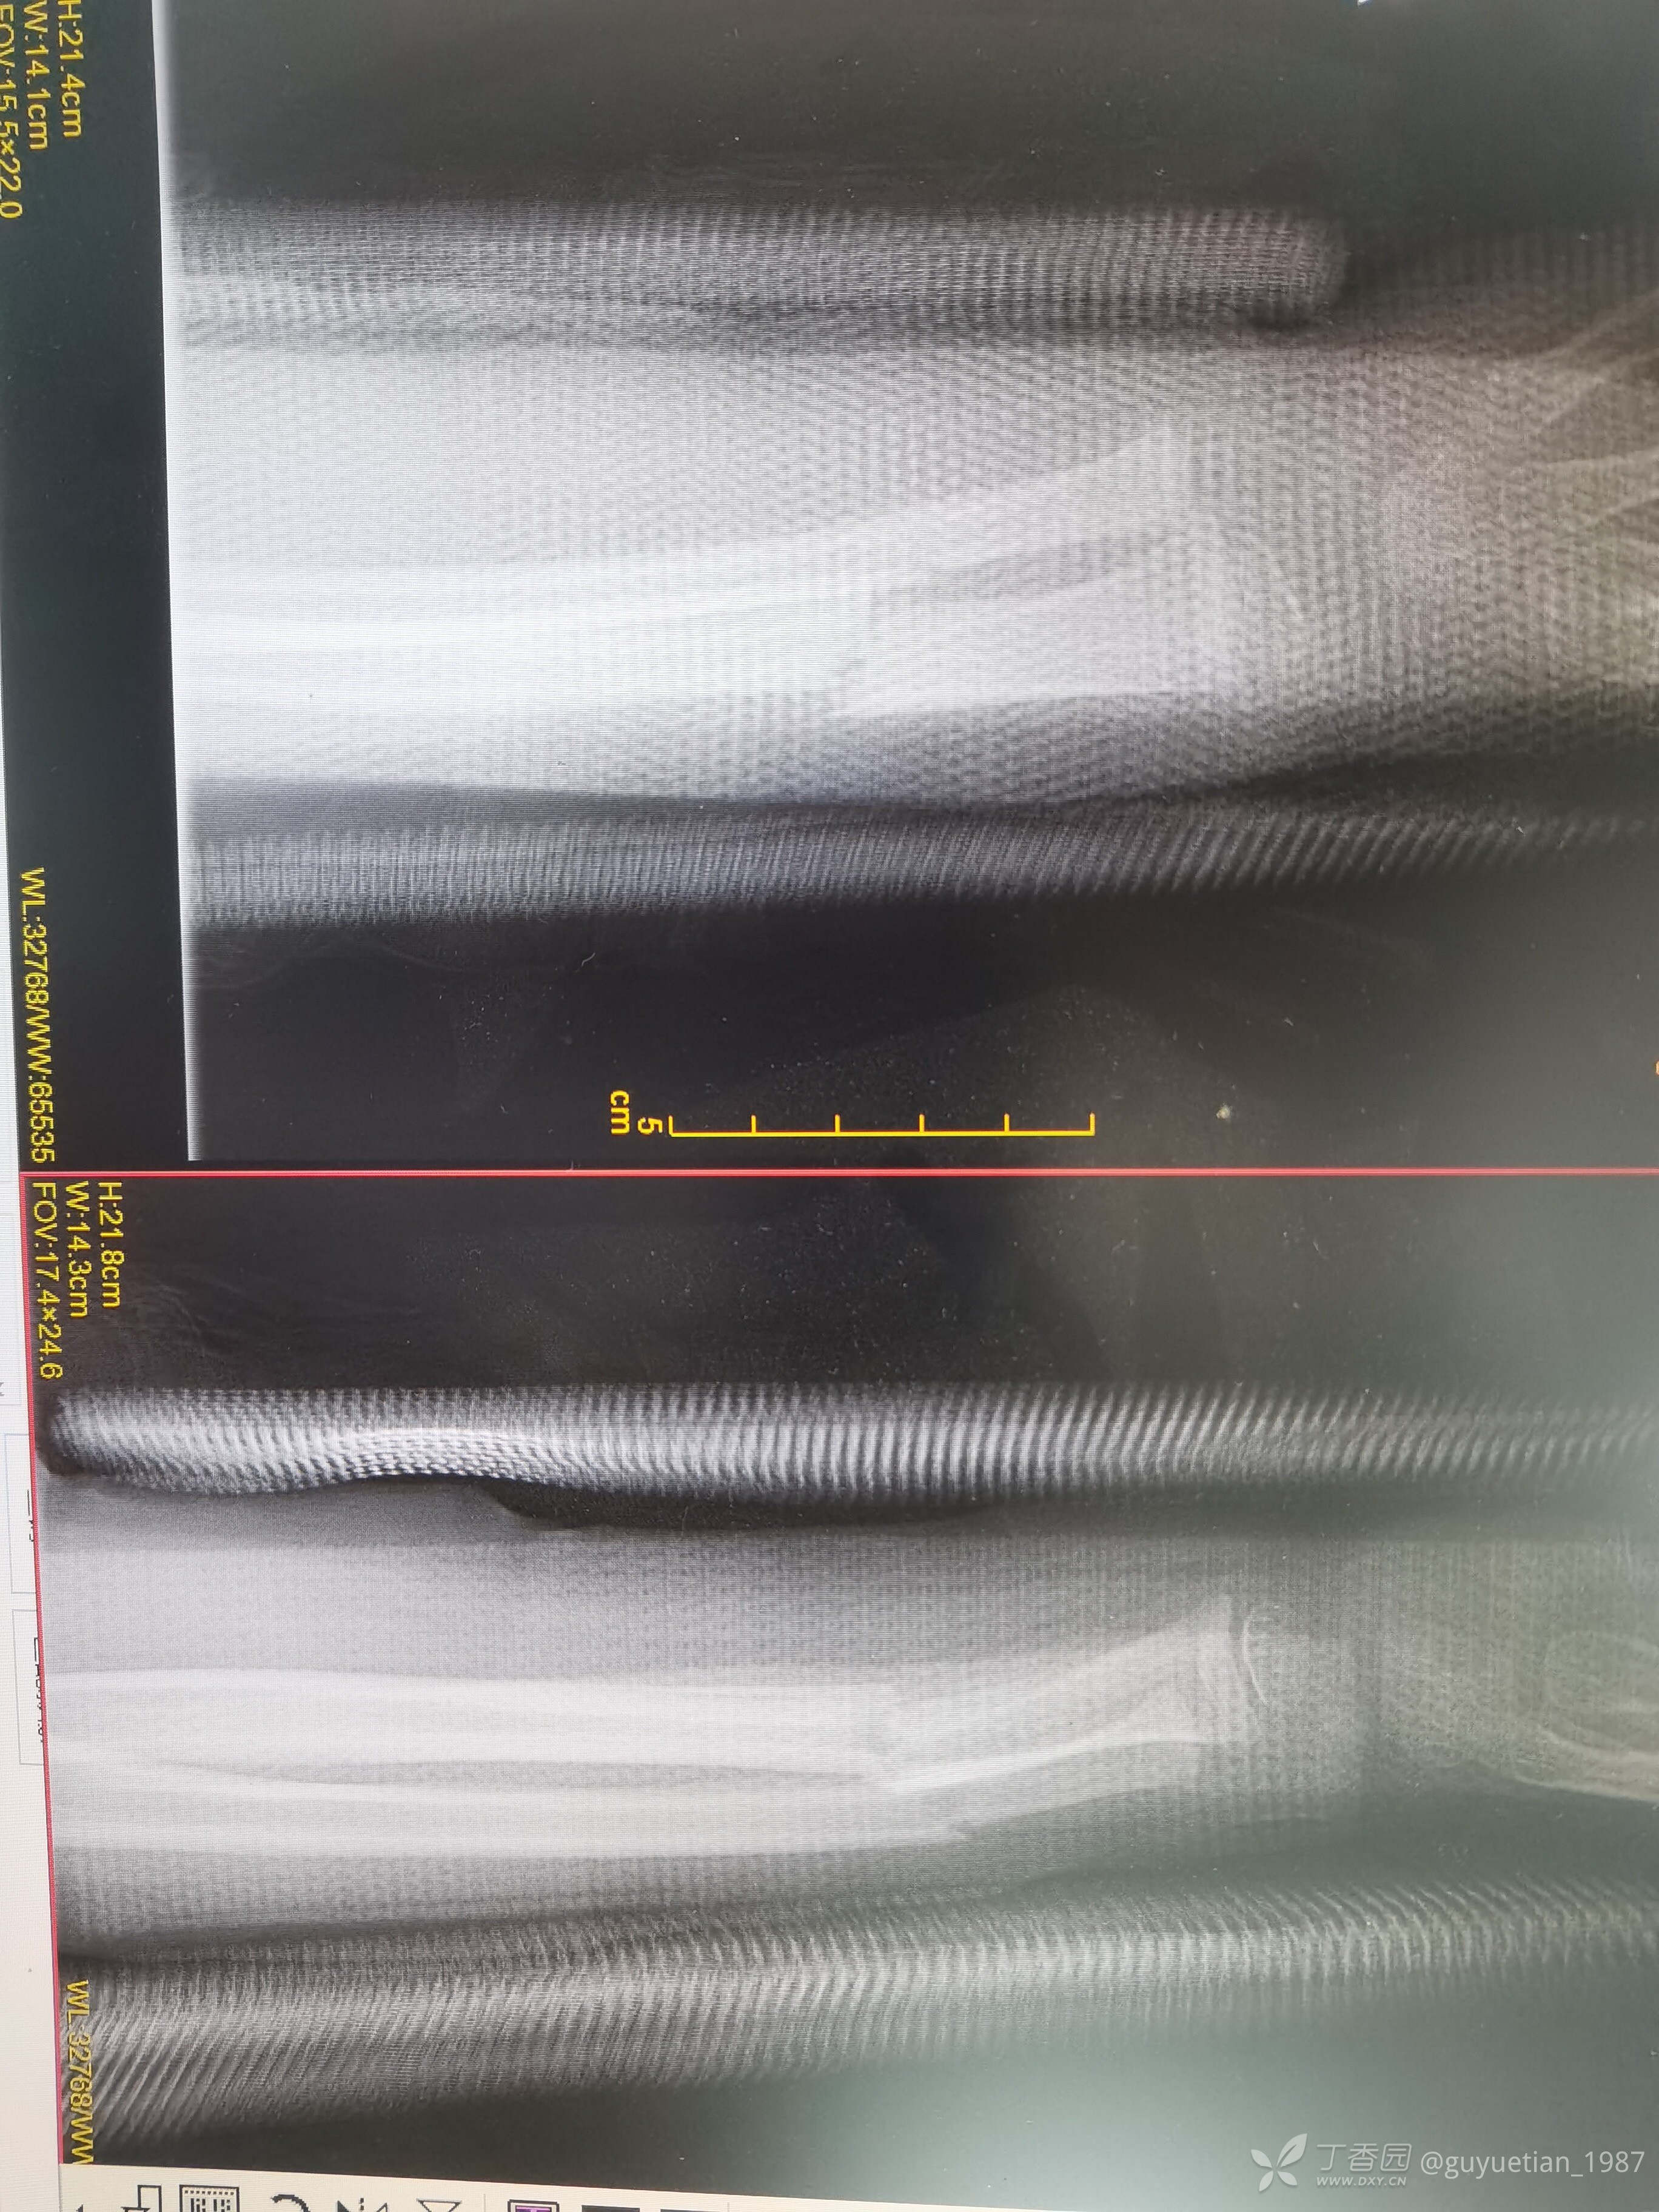

然后就是一周后复诊,侧位像背侧成角。门诊医生斩钉截铁告知这样的位置必须要手术治疗。犹豫后又电话联系再次找到我,再次纠正力线,背侧加了块压垫。复片后力线还行,但是感觉到家属开始犹豫了(门诊是一位资深老医生,专做保守,当地小有名气,说话当然比我有分量),再次坐下来跟爸爸沟通病情,还是让他自己做出选择,手术还是保守?利弊让他自己权衡,当然个人还是希望他保守,对于这个年龄孩子能不手术尽量不要手术(心底知道保守肯定没有问题),适时掏出手机给他看了曹老师的保守治疗典型病例给家属来颗定心丸。